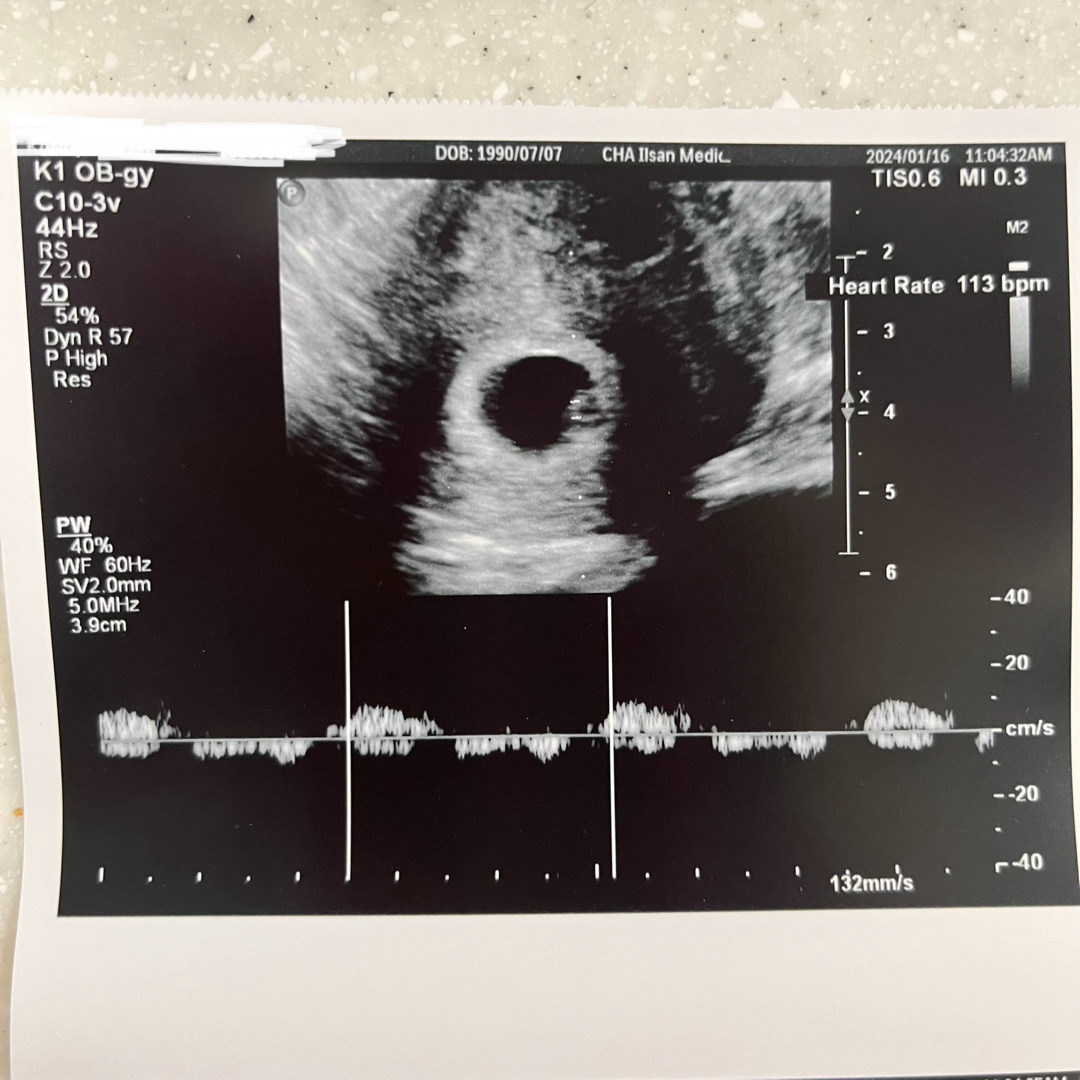

오늘 6주5일차 심장소리 듣고왔어요,

심장소리는 보통 말발굽소리 기차소리로 나눠진다고 하는데 제 뱃속에 있는 아가는 일정한 소리는 잘냈지만 무슨 소리인지는 잘 모르겠어요~~~ ㅋㅋㅋ 주수에 맞게 잘크고 있고 피고임도 없다며 아주 좋다고 하셨는데… 헤헤^_^❤️ 괜찮은거겠죠??? 코딱지만한게 심장움직이는게 보이니까 아주 심쿵 그 자체였어요..💖💖💖💖 우리 다들 건강하게 키워보자구요~☺️

애기집도 심장박동 모양도 귀여워요~🥰